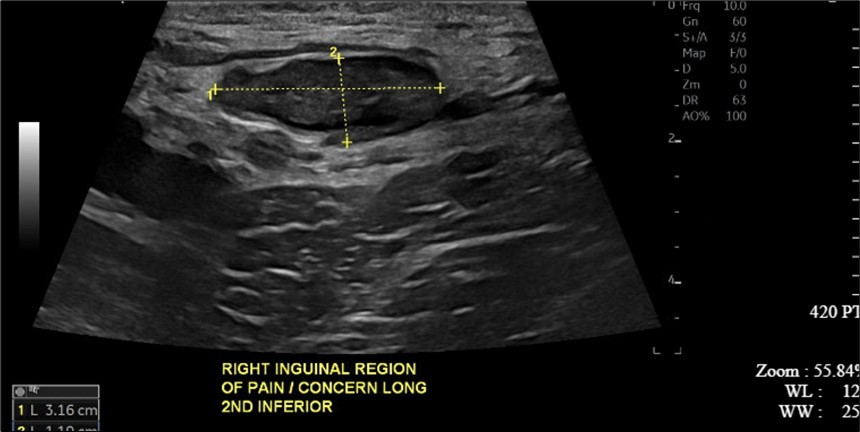

A 34-year-old male presented to the Emergency Department with complaints of large right-sided scrotal swelling, accompanied by scrotal discomfort. The patient’s past medical history was remarkable for a right-sided inguinal hernia, which had been present for several years and was repaired via right open herniorrhaphy with mesh placement three months prior. Physical examination prior to the herniorrhaphy revealed a large inguinoscrotal swelling, measuring 5 inches by 6 inches. During the herniorrhaphy, a very large hernia sac was encountered that could not be fully dissected from the cord structures and required placement of two large meshes; however, the testicles were successfully reduced back into the scrotum. Ultrasound of the right testicle revealed a large hypoechoic space with a complex collection and posterior displacement of the testicle, indicating a possible hydrocele (Figure 1, Figure 2, Figure 3, Figure 4). The patient was taken to the operating room for a right hydrocelectomy. During the procedure, it was noted that the penis was buried within the scrotal swelling, necessitating the placement of a Foley catheter to identify surrounding structures. Upon incision through the Dartos fascia, significant fibrotic tissue and fluid were encountered, making it difficult to maneuver around the hydrocele sac. Upon incising the hydrocele sac, a large collection of thick, dark brown fluid resembling old blood clots was immediately aspirated. Approximately 2 liters of fluid were drained from the sac. After identifying the testicle and cord structures, the proper placement of the testicle within the scrotum was verified. Due to excessive scrotal skin, a scrotoplasty was performed prior to suturing the scrotal skin and fascia (Figure 5). The postoperative hospital course was unremarkable. The patient was discharged with plans to return to the clinic for follow-up with the surgeon.

Figure 3.Ultrasound imaging in the transverse plane of the right inguinal region and underlying soft tissue.